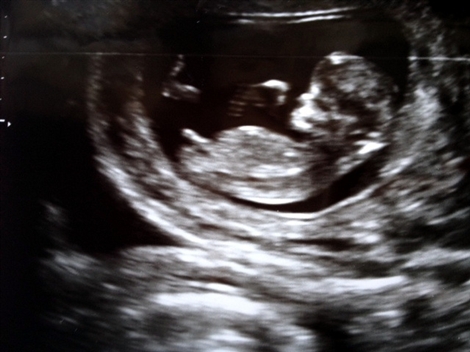

22.8.2012 “Äidin masussa on tyttö!” Ei edelleenkään uutisia Rositan vasikkarintamalla, mutta muita uutisia kyllä, nimittäin ihmisvauvauutisia. Kävin… 31